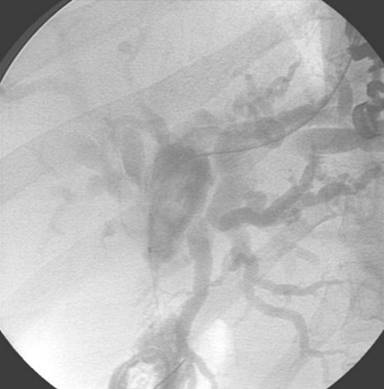

Contrast was injected to demonstrate the jejunal position of the guidewire, and showing the length of the stenosis (Figure 2). A 6 mm guidewire balloon dilation was performed, followed by the placement of a partially covered self-expandable metallic stent (10x60 mm, Wallflex, Boston Scientific, Natick, MA, USA), across the anastomosis (Figure 3). Adequate contrast drainage was observed (Figure 4).

|

Figure 2. Contrast passing to the jejunum, demonstrating the adequate positioning of the guidewire. |